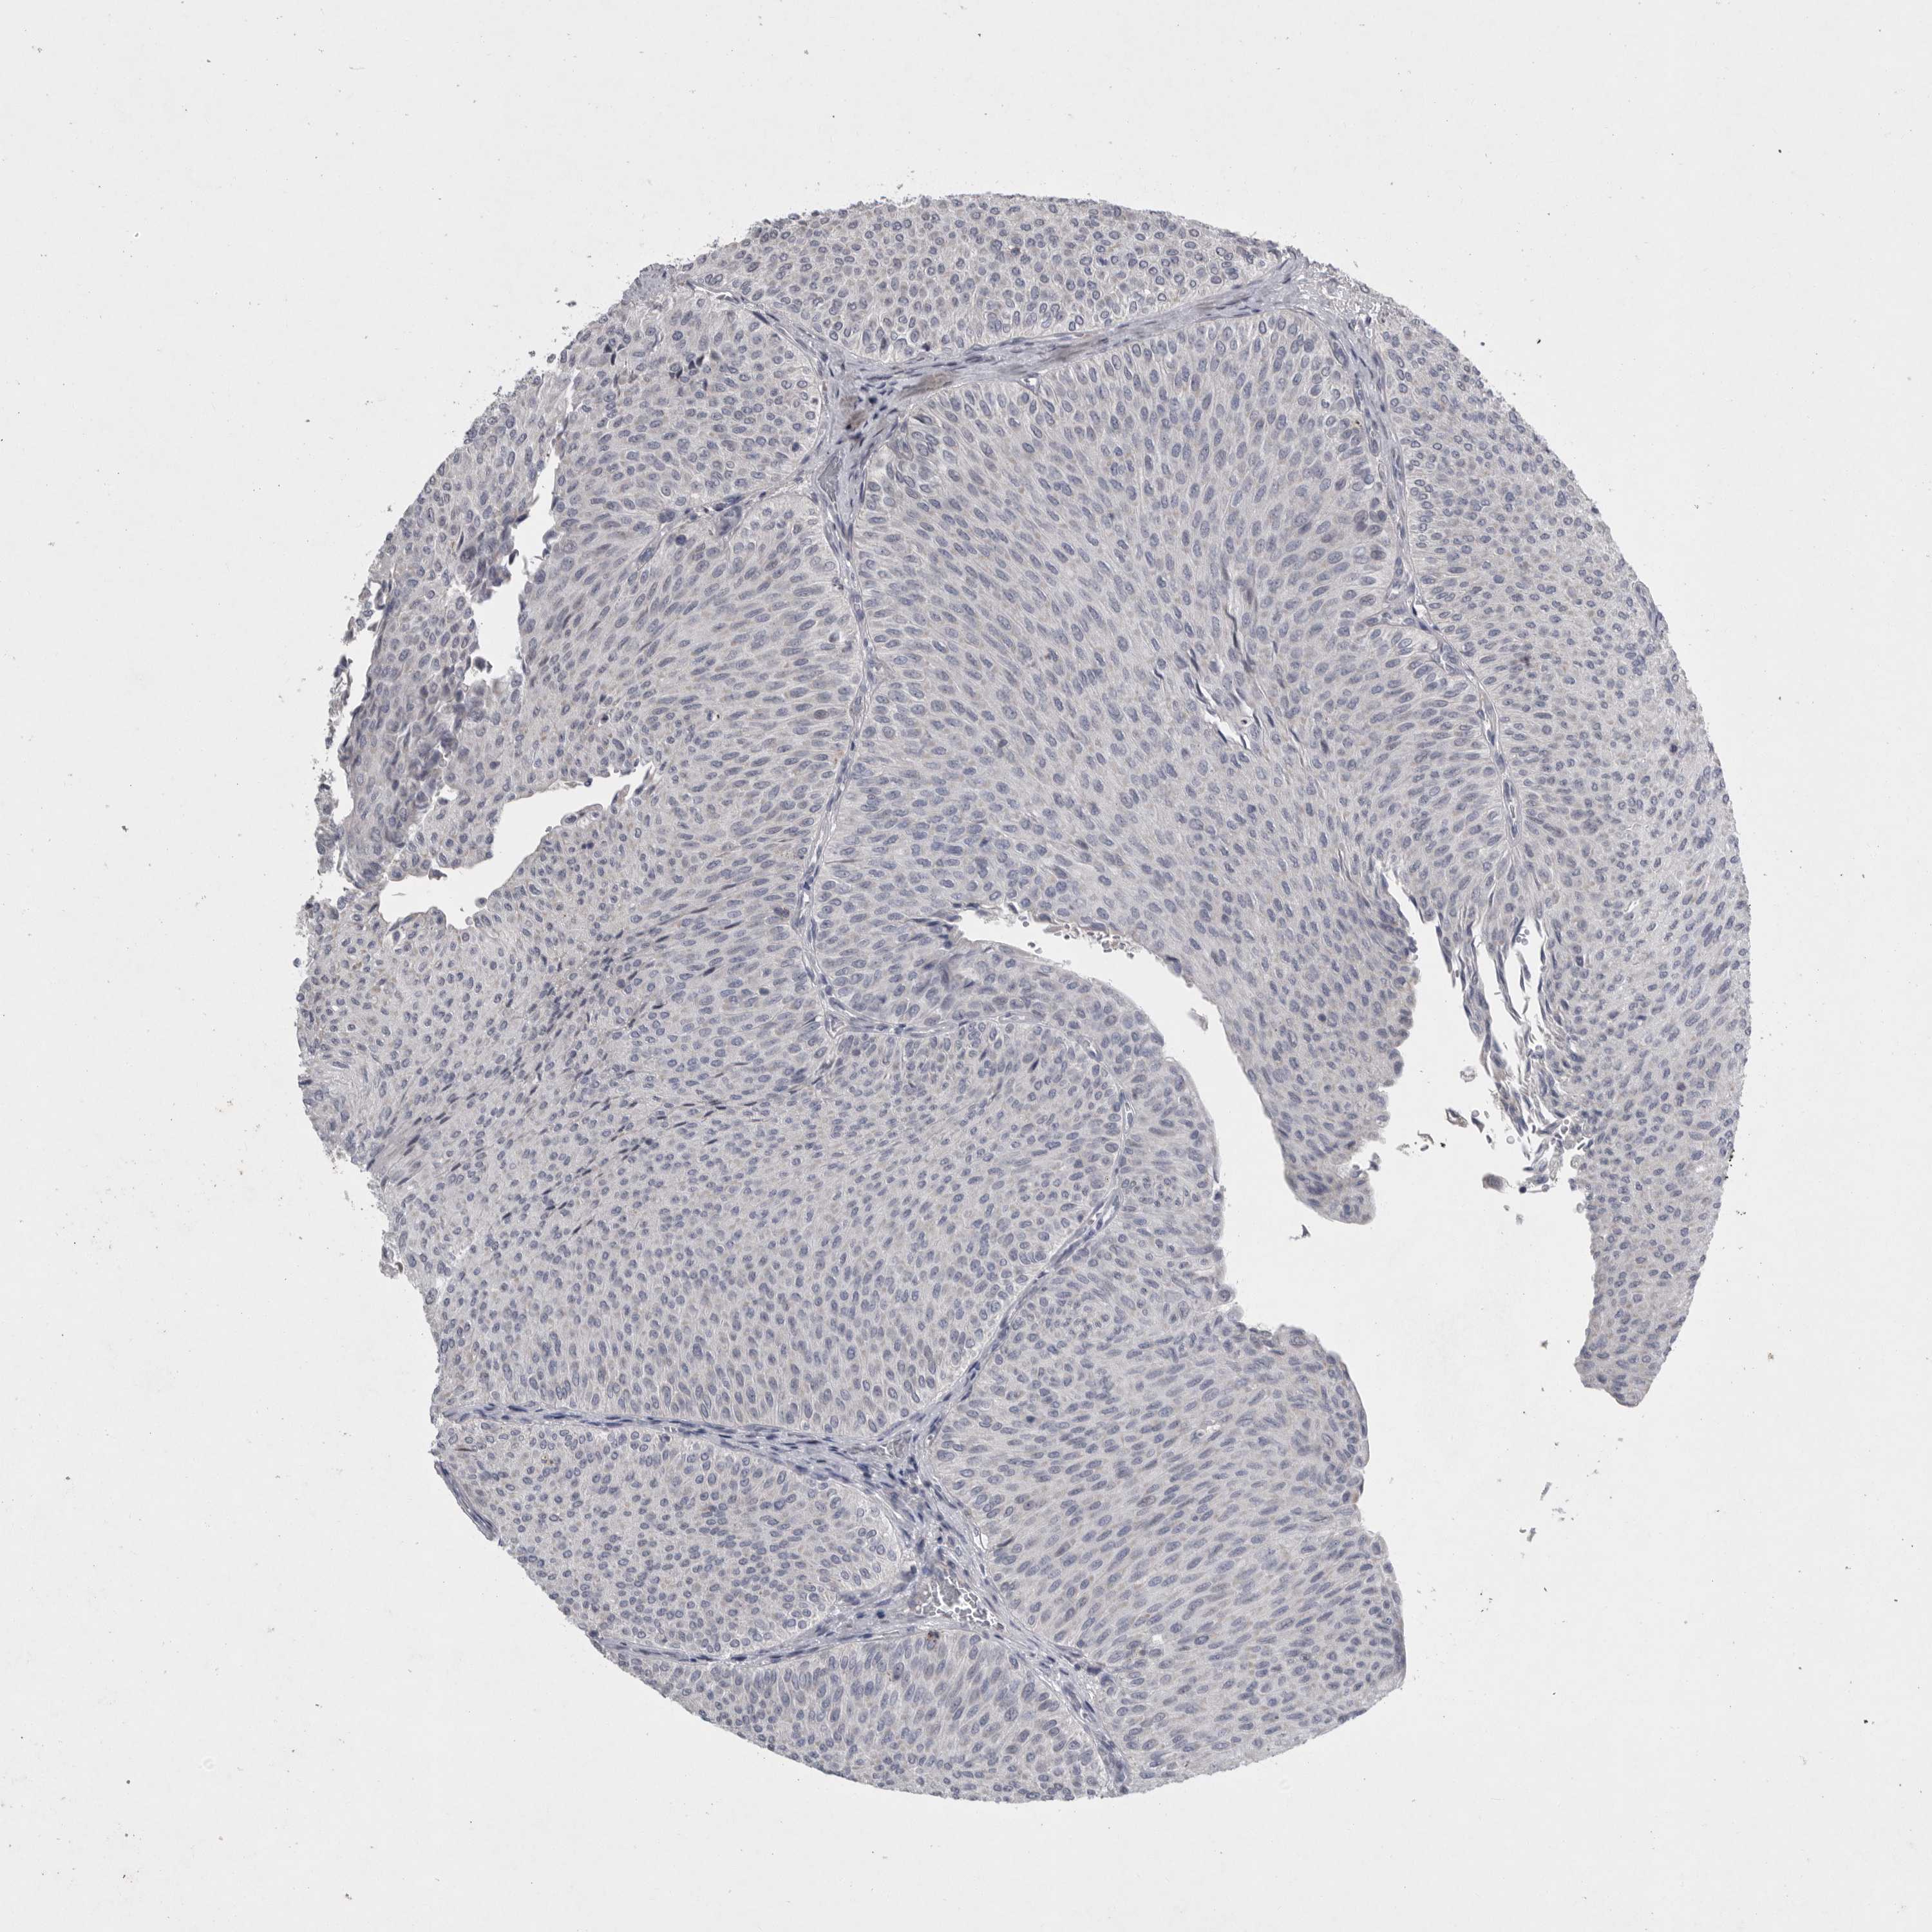

UROTHELIAL CANCER - Protein expressioni

A mouse-over function shows sample information and annotation data. Click on an image to view it in a full screen mode. Samples can be filtered based on level of antibody staining by selecting one or several of the following categories: high, medium, low and not detected. The assay and annotation is described here.

Note that samples used for immunohistochemistry by the Human Protein Atlas do not correspond to samples in the TCGA dataset.

Antibody stainingi

Antibody staining in the annotated cell types in the current human tissue is reported as not detected, low, medium, or high, based on conventional immunohistochemistry profiling in selected tissues. This score is based on the combination of the staining intensity and fraction of stained cells.

Each image is clickable and will lead to virtual microscopy that enables deeper exploration of all samples and also displays staining intensity scores, fraction scores and subcellular localization as well as patient and tissue information for each sample.

Antibody HPA027367

Antibody HPA027396

Antibody CAB005036

Staining

High

Medium

Low

Not detected

Intensity

Strong

Moderate

Weak

Negative

Quantity

>75%

75%-25%

<25%

None

Location

Nuclear

Cytoplasmic/membranous

Cytoplasmic/membranous,nuclear

Urothelial carcinoma, Low grade

Urothelial carcinoma, High grade